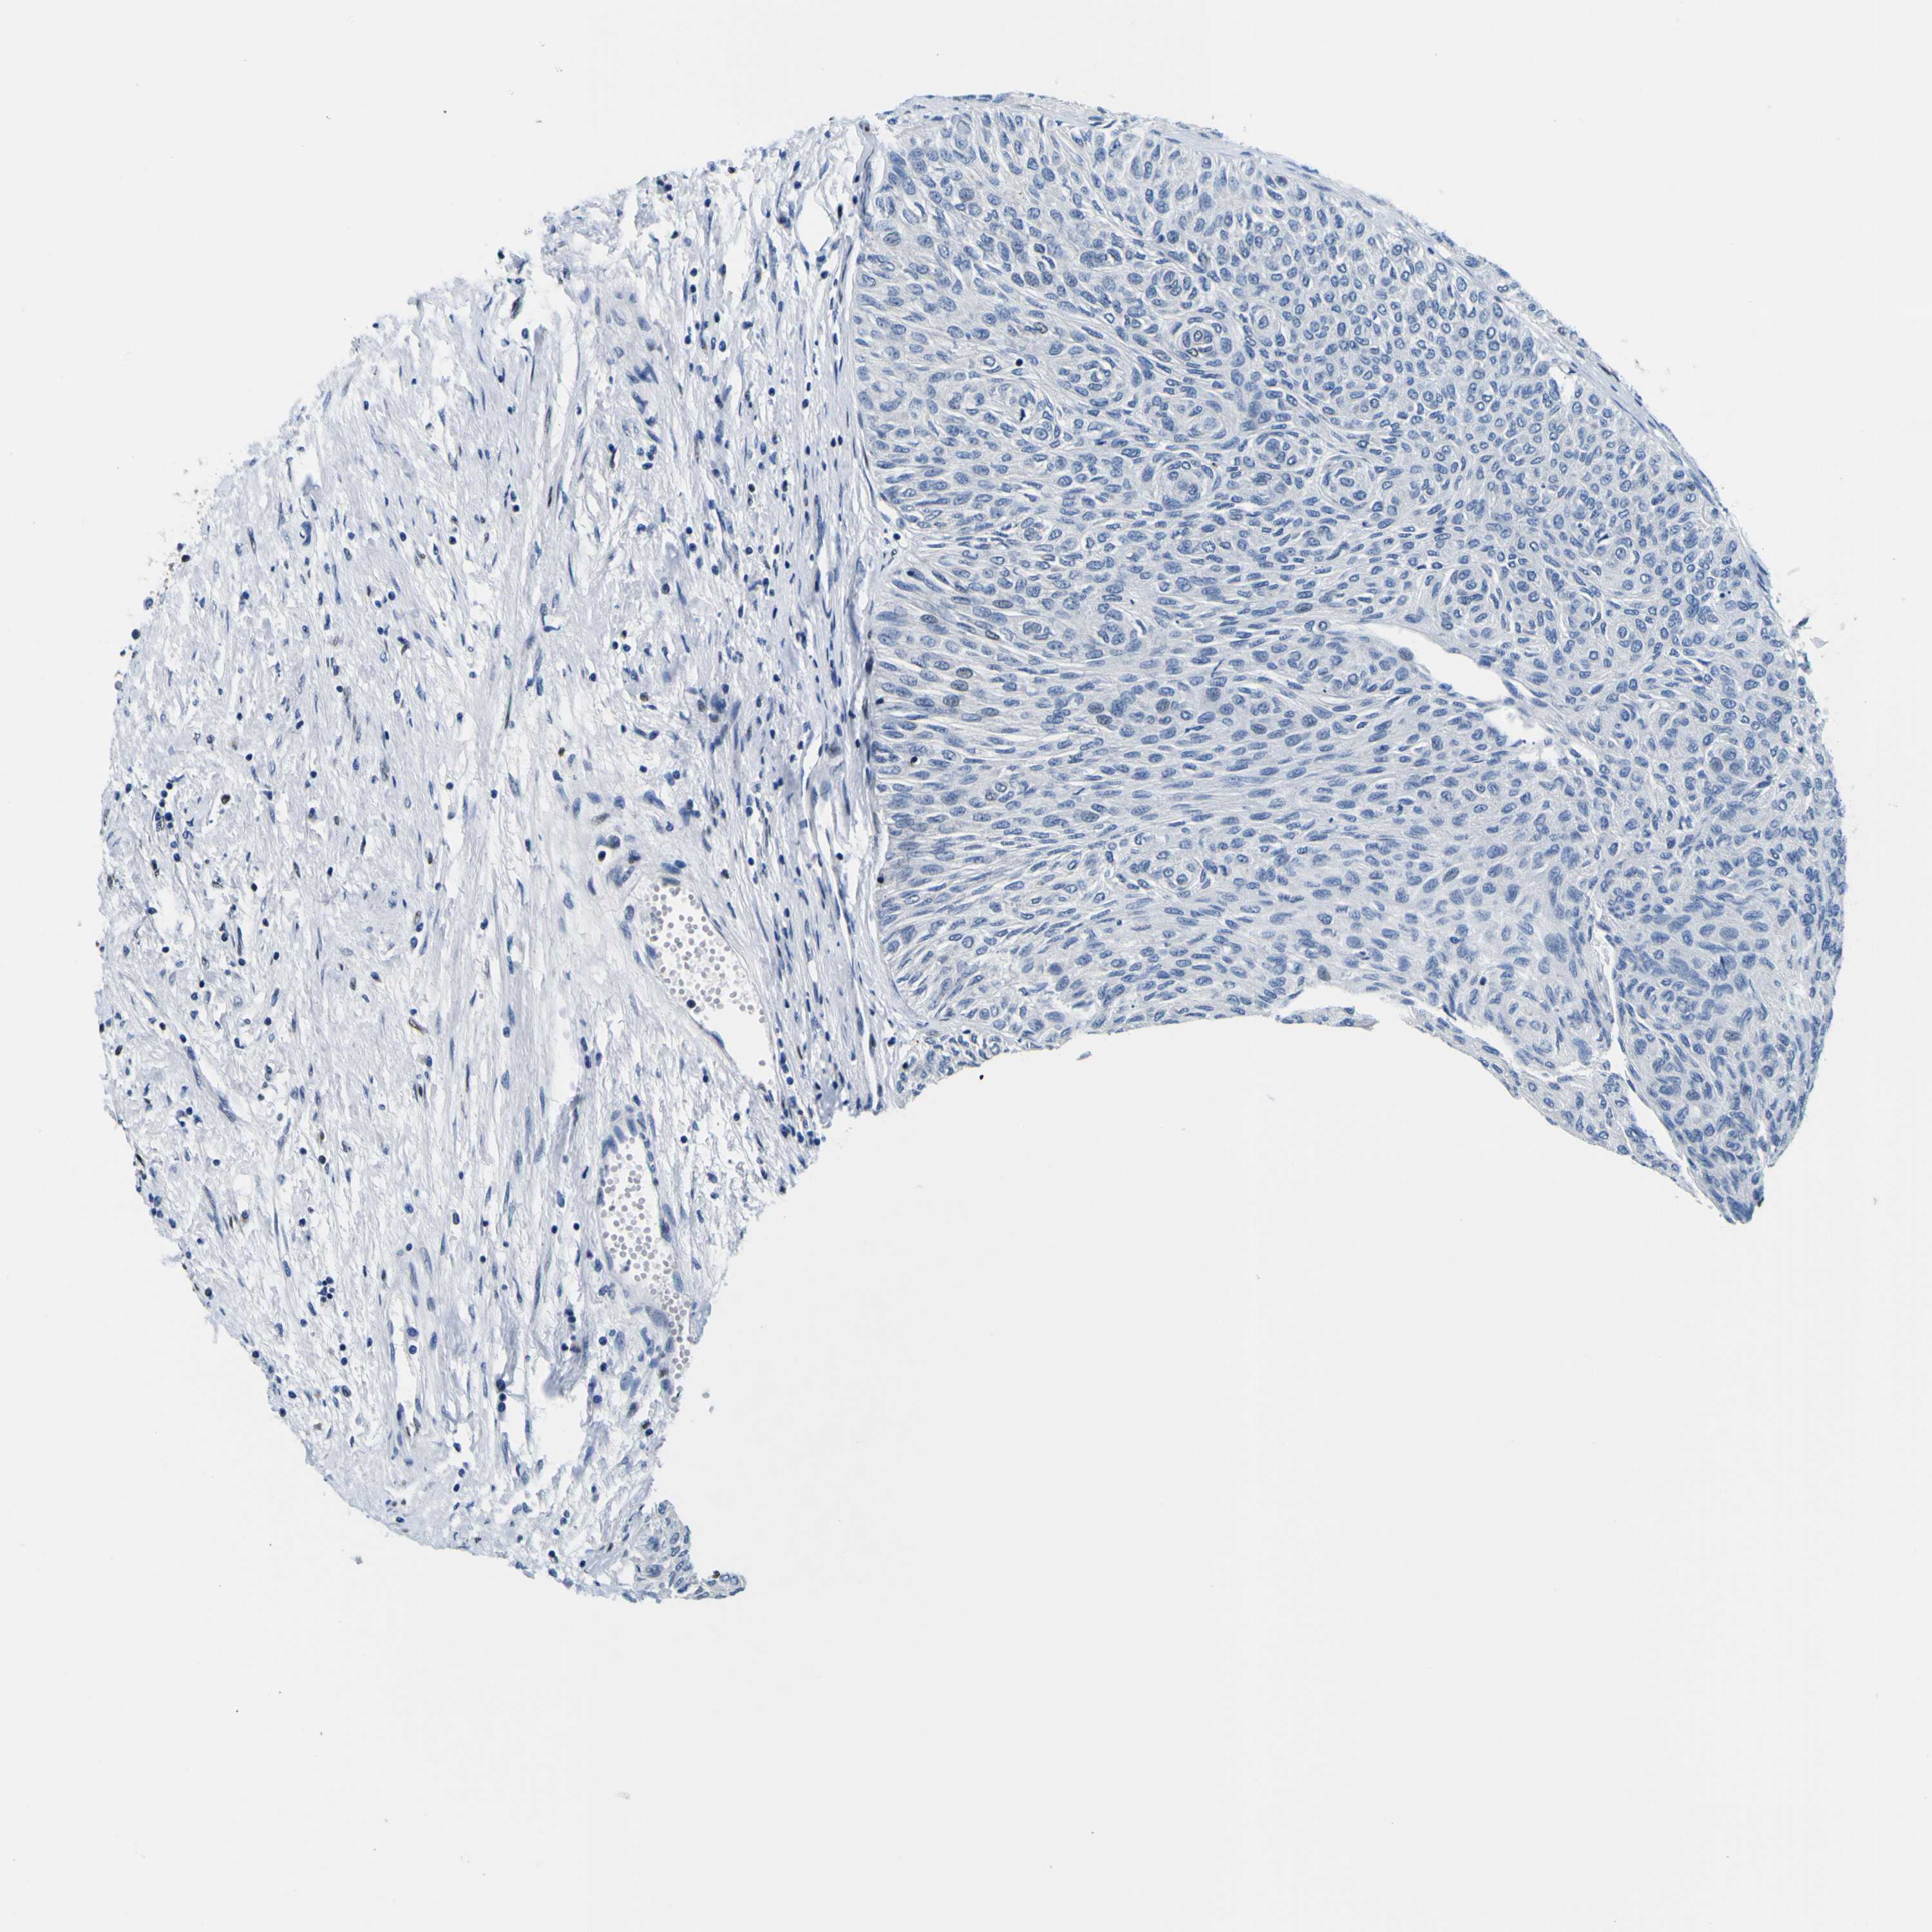

UROTHELIAL CANCER - Protein expressioni

A mouse-over function shows sample information and annotation data. Click on an image to view it in a full screen mode. Samples can be filtered based on level of antibody staining by selecting one or several of the following categories: high, medium, low and not detected. The assay and annotation is described here.

Antibody stainingi

Antibody staining in the annotated cell types in the current human tissue is reported as not detected, low, medium, or high, based on conventional immunohistochemistry profiling in selected tissues. This score is based on the combination of the staining intensity and fraction of stained cells.

Each image is clickable and will lead to virtual microscopy that enables deeper exploration of all samples and also displays staining intensity scores, fraction scores and subcellular localization as well as patient and tissue information for each sample.

Antibody HPA001853

Antibody HPA012292

Antibody CAB000330

Staining

High

Medium

Low

Not detected

Intensity

Strong

Moderate

Weak

Negative

Quantity

>75%

75%-25%

<25%

None

Location

Nuclear

Cytoplasmic/membranous

Cytoplasmic/membranous,nuclear

Urothelial carcinoma, High grade

Urothelial carcinoma, Low grade